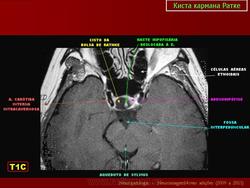

ГМ. Киста кармана Ратке. +

Киста кармана Ратке

Ратке карман (sacculus hypophysialis; М. Н. Rathke, нем. анатом). Выпячивание эпителия задней стенки ротовой полости зародыша на границе с глоткой; зачаток аденогипофиза. Синоним: гипофизарный карман.